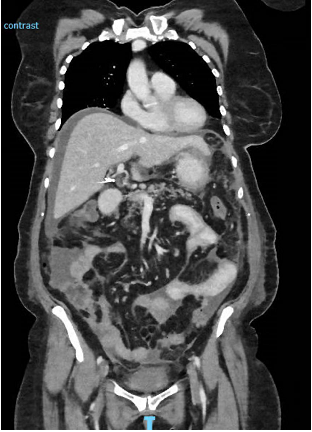

A previously well 66-year-old lady presented to a metropolitan tertiary hospital with a 3-month history of lower abdominal pain that had worsened in the preceding week. On examination, she was tachycardic with a heart rate of 126 beats/minute and had a distended, tender abdomen but was non-peritonitic. Her history was significant for ischaemic heart disease for which she underwent percutaneous coronary intervention with stent insertion a year prior, as well as a previous cholecystectomy. Investigations revealed elevated inflammatory markers with a white cell count of 13.7x109/L and CRP of 185mg/L. An abdominal computed tomography (CT) scan interestingly demonstrated a moderate amount of free peritoneal fluid and associated stranding without a clear source (Figure 1). Ascites of unknown aetiology was diagnosed on the CT, and given her tender abdomen and raised inflammatory markers, she was admitted under the Acute Surgical Unit for further investigation.

Figure 1 Coronal slice of CT abdomen/pelvis on initial presentation to hospital with evidence of ascites and peritoneal stranding.